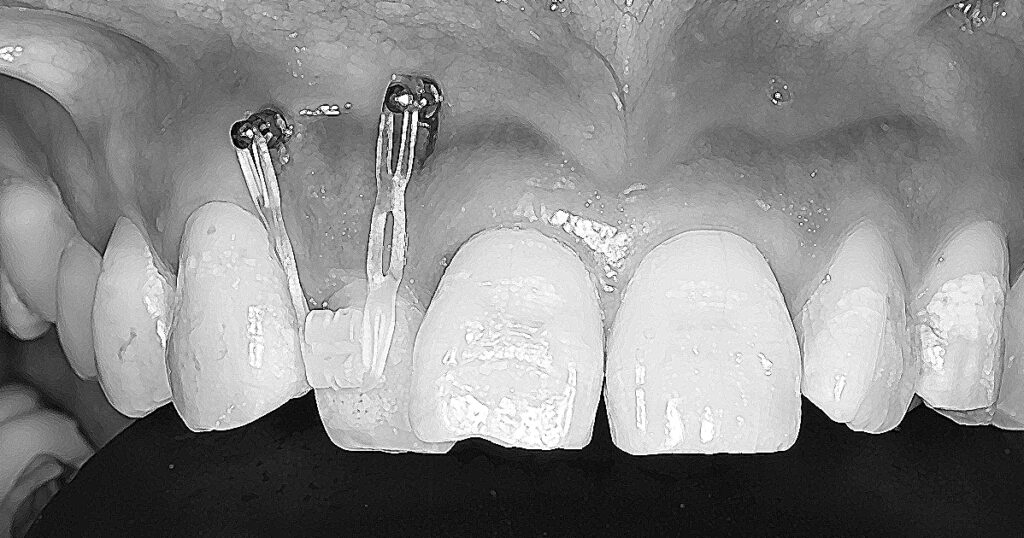

• 歯周病治療と部分矯正後に口腔内スキャンを利用し中切歯の修復

歯周病で歯並びが崩れた前歯を歯周治療と部分矯正後に矯正装置を付けたまま、口腔内スキャナーを使ったデジタル印象にてジルコニアセラミック冠を製作。 同時に3Dプリンター(ステレオリソグラフィー)にて得られた模型を調整して、マウスピースタイプ...